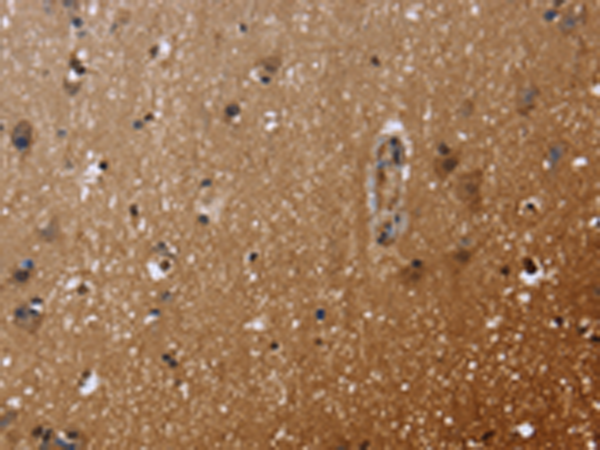

分类: 科研抗体货号: P01425别名: GPRK5; FP2025应用: IHC反应种属: Human, Mouse, Rat